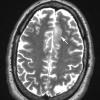

NEOPLASMS (GLIAL)

Astrocytoma, IDH-mutant, WHO Grade 2 (9)